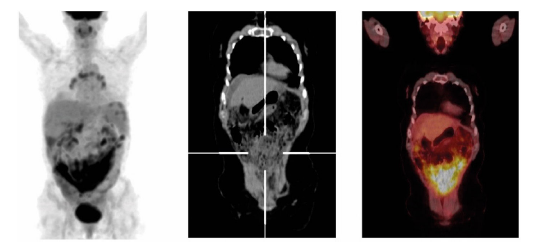

El epiplón mayor es rico en tejido linfoide, absorbe líquido peritoneal y es un sitio frecuente de siembras neo-plásicas. En la afectación del omento, el PET/CT 18F-FDG muestra engrosamiento de este, hiperdensidad, y nodularidad, con captación elevada y difusa de FDG (fig. 2). Los nódulos neoplásico umbilicales, llamados nódulos de Sister Mary Joseph, están localizados en la pared anterior del abdomen y son signo de compromiso abdominal maligno 9. El PET/CT 18F-FDG puede detectar lesiones de difícil diagnóstico, debido a su ubicación inusual o por su pequeño tamaño. En la lesión con componente quístico y sólido, la captación anormal se aprecia sobre el componente sólido.

Figura 2 Carcinoma seroso de ovario de alto grado en recaída. Múltiples nódulos peritoneales hipermetabólicos con compromiso subcapsular hepático, esplénico, con extenso compromiso difuso pélvico (SUVmx: 10.13). Se observa patrón de captación principalmente difuso.